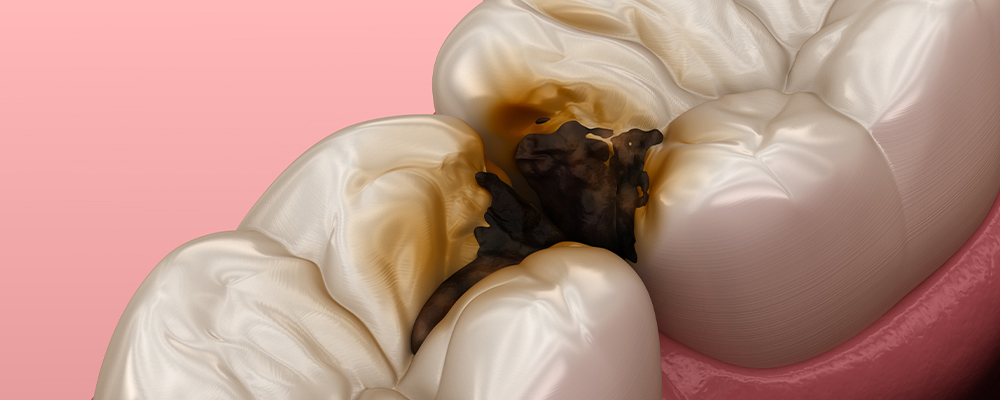

② 虫歯・歯周病になるリスクが高い場合

親知らずが斜めに生えていると、歯ブラシが届きにくくなります。その結果、手前の大切な奥歯までむし歯や歯周病になることがあります。特に横向きに埋まっているケースでは、知らないうちに手前の歯の根元が溶けてしまうこともあります。親知らず1本の問題ではなく、「その隣の健康な歯を守るかどうか」という視点が大切です。